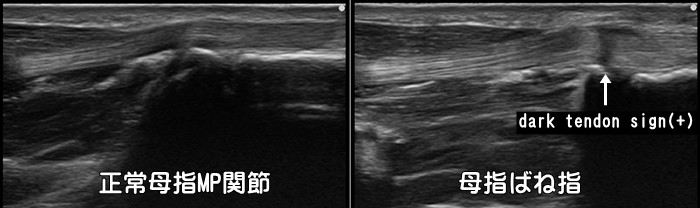

指の腱鞘炎・ばね指

正常な腱は楕円形ですが、炎症を起こした腱は肥大し円形になります。また腱周囲の腱鞘に水が溜まり黒く描出されます。発症頻度は第1→3→4指の順です。腱が肥大するとプローブからの超音波が乱反射してうまく返ってこない為に一部が黒く描出されるdark

tendon signが見られます。※tendon=腱